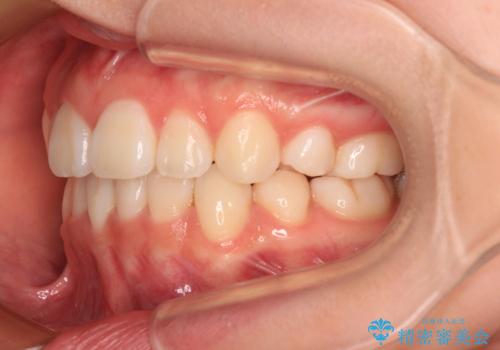

- 歯のデコボコや八重歯、クロスバイトを気にして来院された患者様です。

上下左右第一小臼歯4本を抜歯し、ワイヤー装置にて歯列を整え、さらには少しでも口元を引っ込めるよう矯正治療を行うこととしました。

上下の骨格での左右差が小さかったことと、抜歯矯正であったことで、上下正中の位置をきれいに合わせることができました。